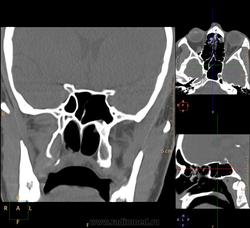

Ни одной, а точнее, спонгиоз (может, воздушность и была когда-то). Преобладает у возрастных пациентов, но встречается в любом возрасте:

И еще спонгиоз:

Спонгиоз - это некорректный самопальный термин)). Долгая беседа с ЛОР-врачом, в итоге сего и родилось такое название. Имеется в виду фиброзное замещение воздушности пазухи в результате хронических воспалительных заболеваний или идиопатически, либо врожденное снижение воздушности за счет неполного рассасывания губчатой костной ткани, что должно предшествовать возникновению нормальной пневматизации. Может, вариант дисплазии, но мне больше нравится как исход фиброзного синусита. Я других толковых объяснений не нашла. blush Если кто поможет с сылками - буду бесконечно благодарна!

Термин "спонгиоз" некорректен. Это не приобретенная патология пазух, не результат инволютивных изменений, а врожденная аномалия, называемая в русскоязычной литературе "незавершенной пневматизацией", а в англоязычной - заключенной (арестованной) пневматизацией: